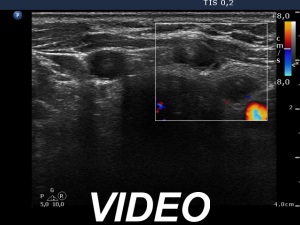

Ultrasound. Connective tissue replaced the thyroid parenchyma in both thyroid beds. There were tiny hypoechoic areas in the right thyroid bed. Two larger hypoechoic lesions were found, one in the isthmus and the other in the left thyroid bed. The latter presented vascularity.

Comment. The presentations of the hypoechoic lesion in all three sites were the same, they differed only in their size. Naturally, the two larger in the isthmus and in the left thyroid bed could cause and did cause concern. Especially that in the left lobe due to its intralesional vascularity. The larger lesions can correspond to small muscle fibers, remnant of the regenerative provess after the surgery but even damaged, non-viable thyroid tissue. Taking the thyroglobulin level into account, the risk of thyroid cancer is minimal but not zero.